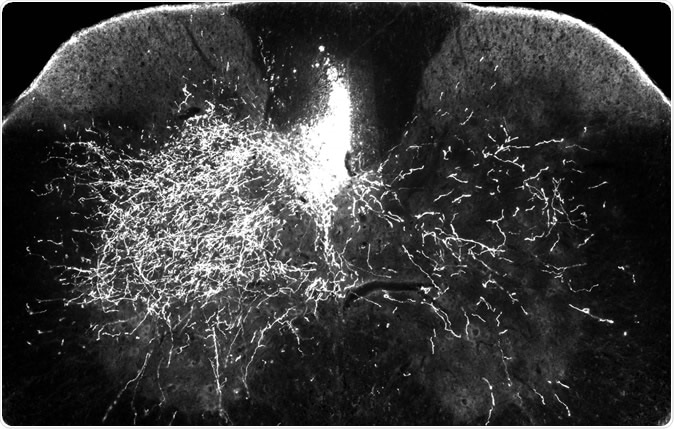

In one of the mouse models for this research, one side of the descending spinal pathway is damaged (above right) while the other side (above left) remains intact. In this image, bright streaks on the right show that in mice treated with gabapentin, descending motor axons are able to sprout to send nerve impulses to the denervated part of the spinal cord – a key step in rebuilding the central nervous system after injury.

For the study the team included mice with spinal cord injury. The mice that had been treated with gabapentin showed around 60 percent improvement in the forelimb functions as seen in a skilled walking test. Mice that served as control and were given a placebo showed a 30 percent improvement in the test said the researchers. They focussed on the nerves that controlled the voluntary movements of the muscles of the body. These nerves mainly are present at the corticospinal tract, they wrote.